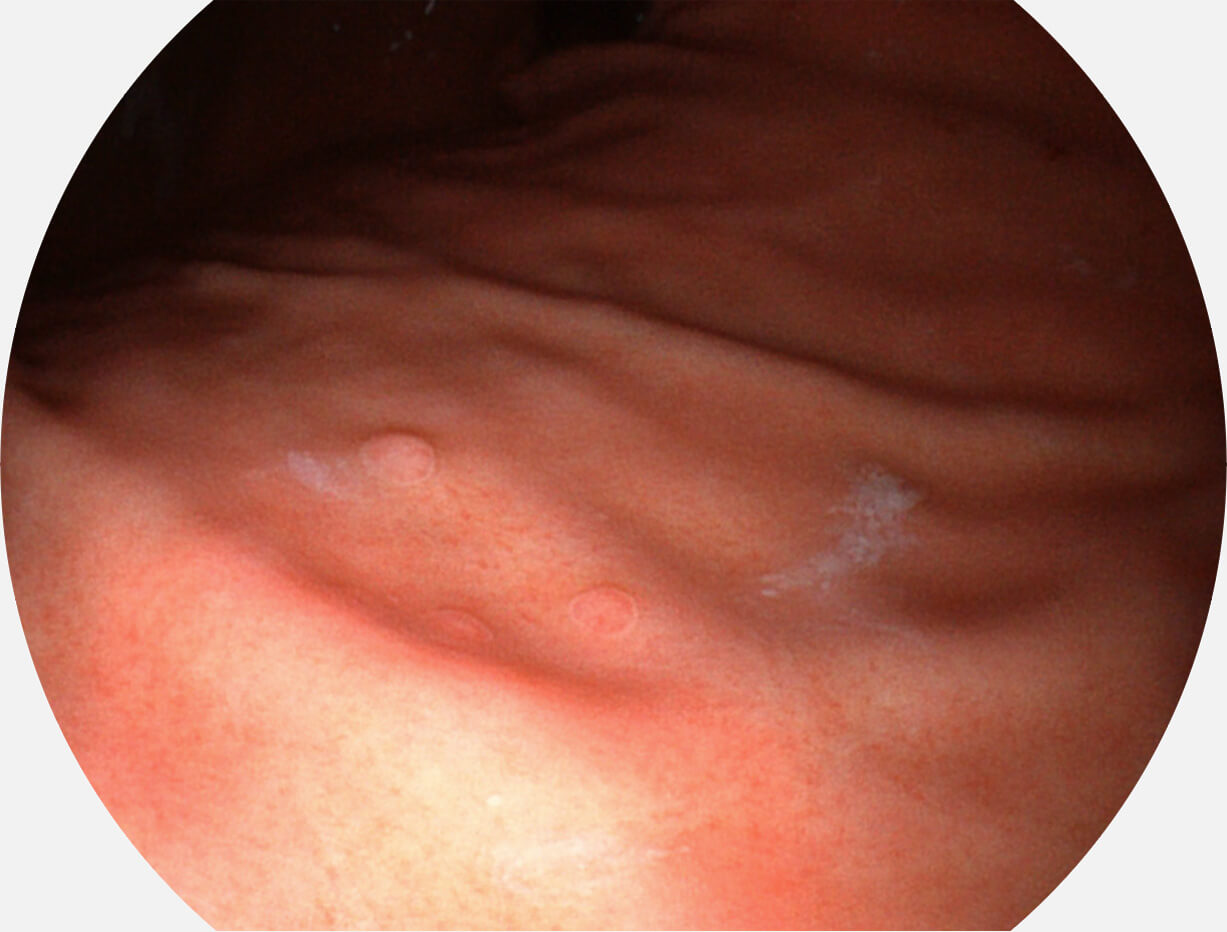

图像具有高亮度、高黏膜血管颜色对比度的特点,且不改变粘液、食物残渣、粪便的基本颜色,可在中远景下进行观察,助力消化道早期疾病的诊断。

SFI图像